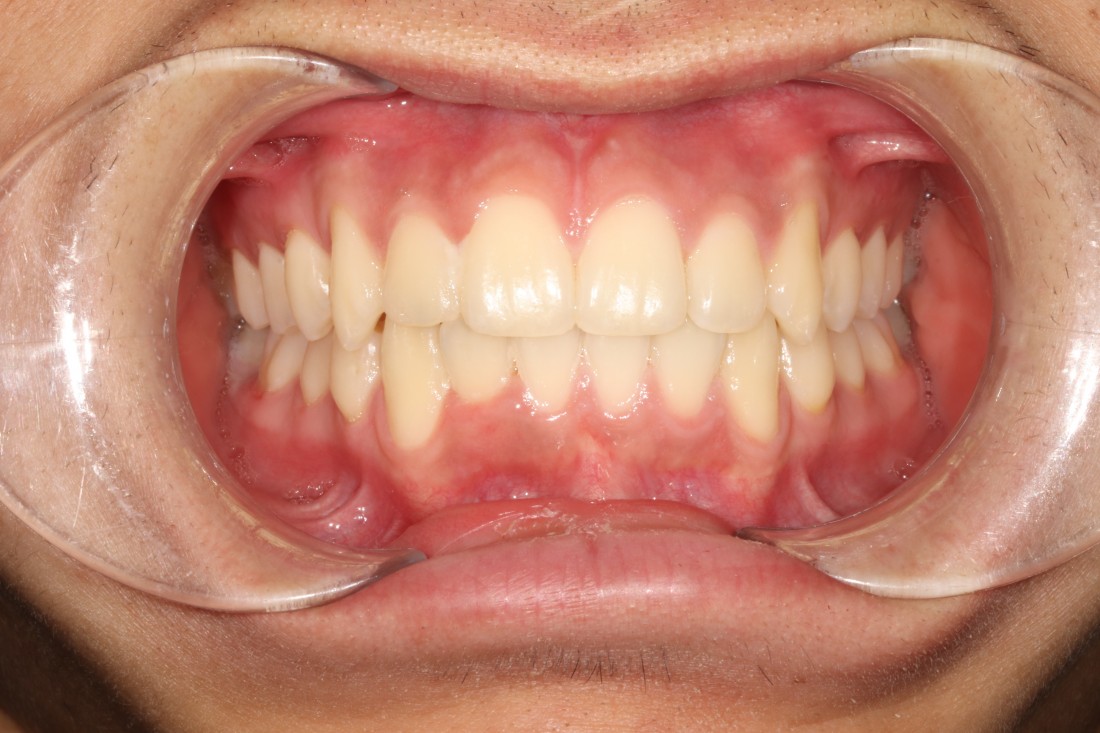

성인이 된 이후에도

과개교합을 방치하게 되면

앞니가 많이 마모되게 되며,

사각턱이 생길 수 있으며

무엇보다 교합이 맞지 않기 때문에

시간이 지날수록 턱관절장애를 유발하게 되어

빠르게 개선해주는 것이 좋습니다.